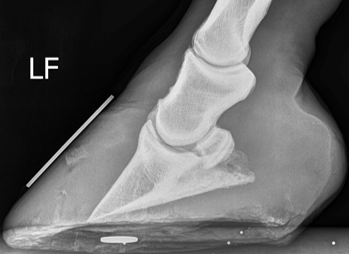

does this horse have laminitis, if so, how can you tell?

yes

and it is

chronic

, the

flick

on the

P3

is indicative of this